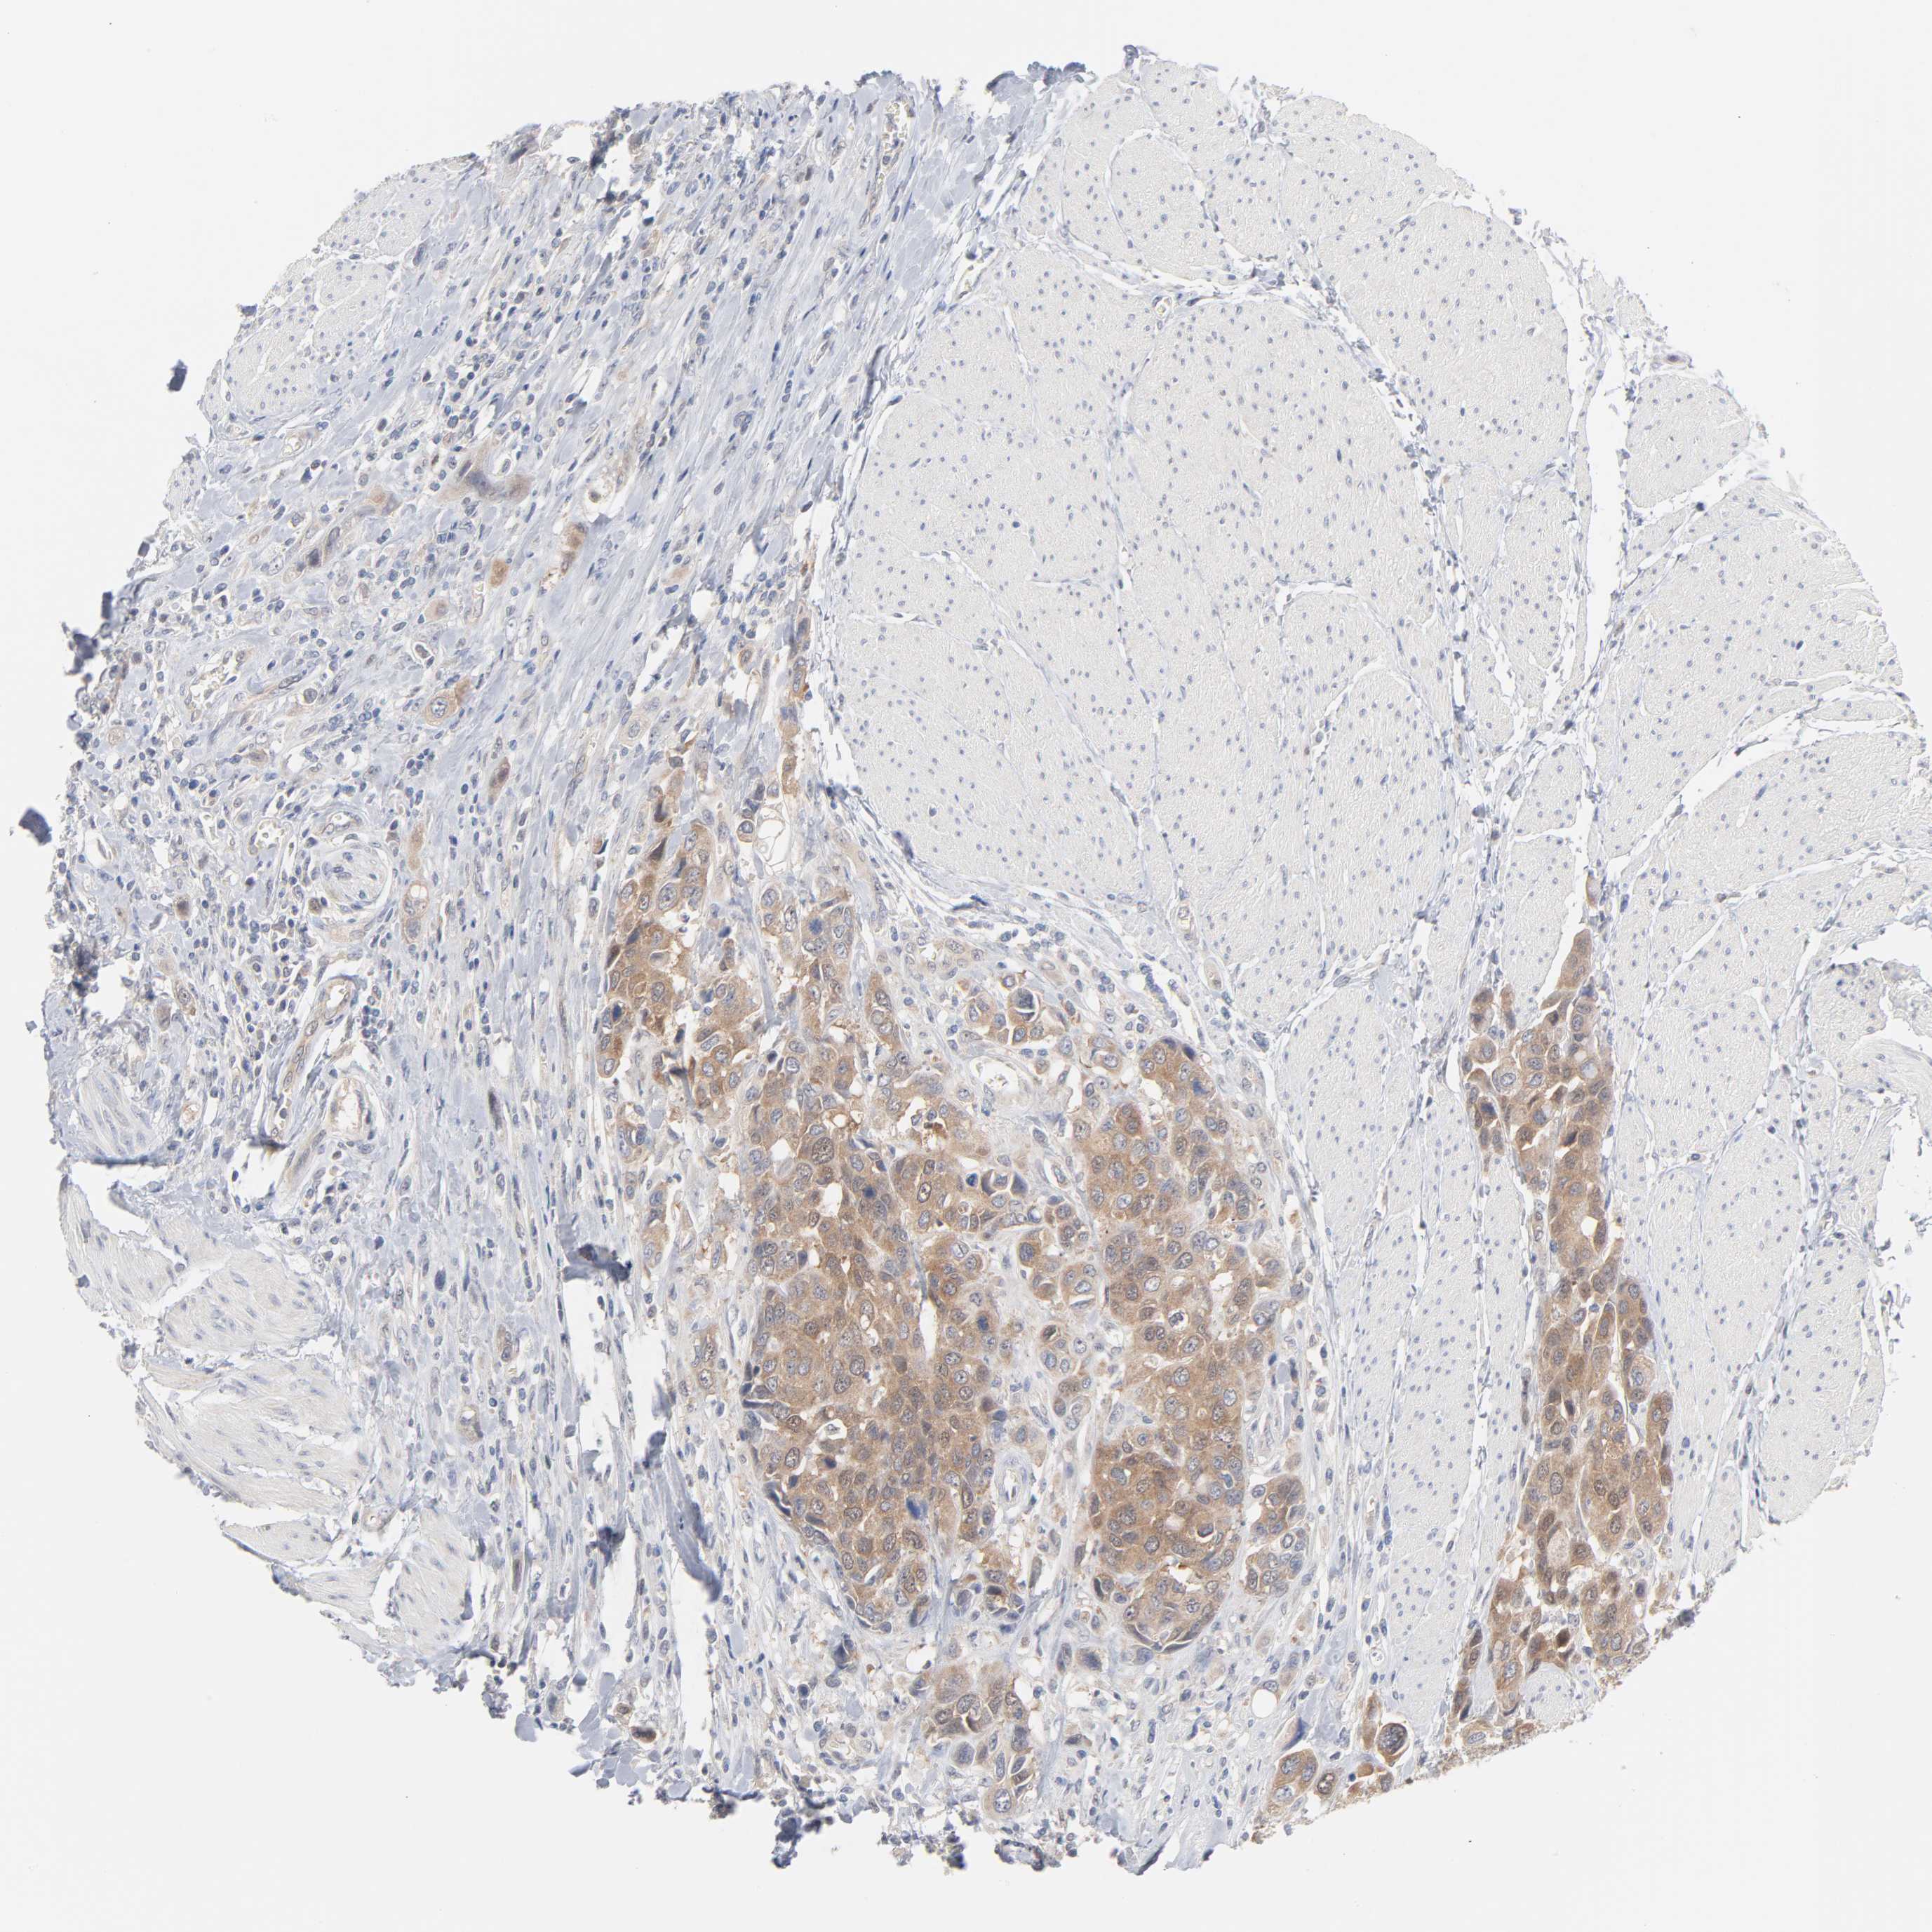

UROTHELIAL CANCER - Protein expressioni

A mouse-over function shows sample information and annotation data. Click on an image to view it in a full screen mode. Samples can be filtered based on level of antibody staining by selecting one or several of the following categories: high, medium, low and not detected. The assay and annotation is described here.

Note that samples used for immunohistochemistry by the Human Protein Atlas do not correspond to samples in the TCGA dataset.

Antibody stainingi

Antibody staining in the annotated cell types in the current human tissue is reported as not detected, low, medium, or high, based on conventional immunohistochemistry profiling in selected tissues. This score is based on the combination of the staining intensity and fraction of stained cells.

Each image is clickable and will lead to virtual microscopy that enables deeper exploration of all samples and also displays staining intensity scores, fraction scores and subcellular localization as well as patient and tissue information for each sample.

Antibody HPA003617

Staining

High

Medium

Low

Not detected

Intensity

Strong

Moderate

Weak

Negative

Quantity

>75%

75%-25%

<25%

None

Location

Nuclear

Cytoplasmic/membranous

Cytoplasmic/membranous,nuclear

Urothelial carcinoma, High grade

Urothelial carcinoma, Low grade